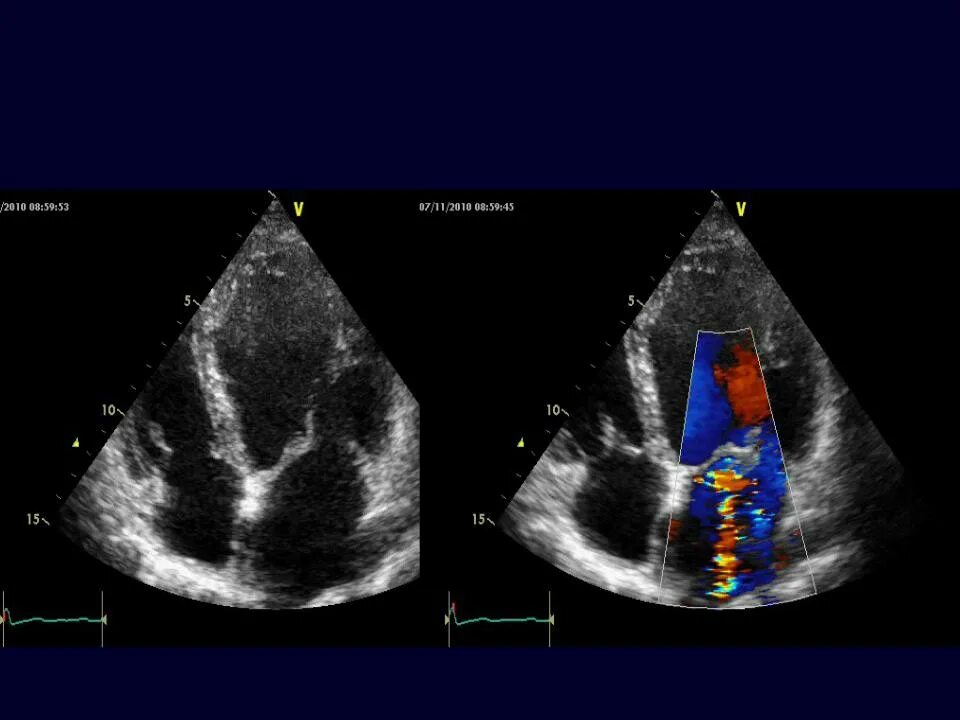

Частичный отрыв